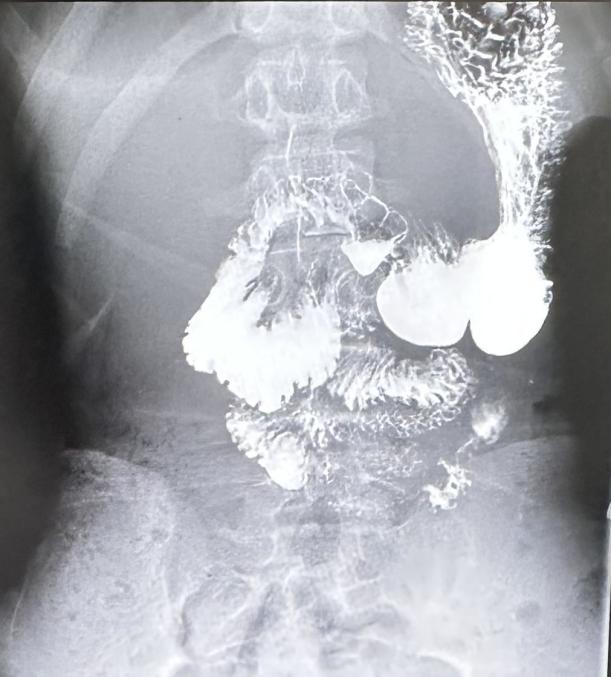

消化道造影显示小乔的十二指肠不完全性梗阻(图2)

经过腹部B超、CT、消化道造影等检查,医生发现小乔的肠系膜上动脉与腹主动脉夹角只有20°,过小的夹角使得十二指肠受到肠系膜上动脉的压迫而产生梗阻(图1-2)。